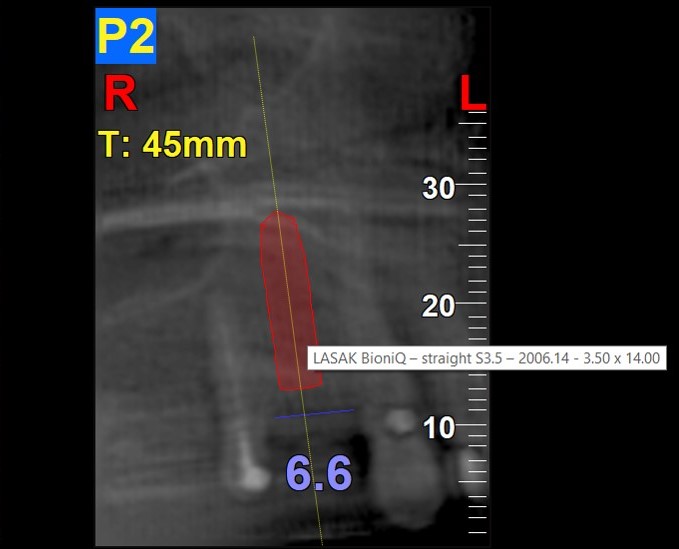

Aufgrund der Messung des Knochenangebots wurde ein 14 mm langes Implantat BioniQ® Straight mit Ø 3,5 mm für Regio 14 eingeplant.

Um die Implantatsetzung so genau wie möglich zu gestalten (angesichts des begrenzten Knochenangebots sowie der Implantatlänge von 14 mm) und um die nahestehende Wurzel des Nachbarzahns zu umgehen, wurde eine kombinierte Operationsschablone entworfen.